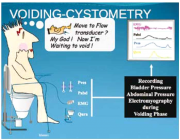

| 06:26, 3 באוגוסט 2014 | נוירוגנית5.png (קובץ) |  |

243 קילו־בייטים | Motyk | 1 | |